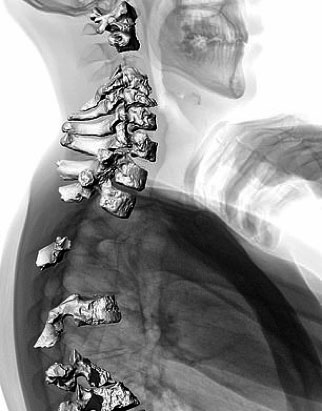

Fig 1 and 2Early reconstructions suggested Neanderthal stood with a hunch. Neanderthal spine (right) superimposed on a scan of the modern human back, highlighting their similarity

The new study shows that their spinal curvature was similar to our own. The Neanderthal spine is shown on right, superimposed on a scan of the modern human back.

The cervical spine can be seen superimposed over a modern human scan, revealing a similar curvature